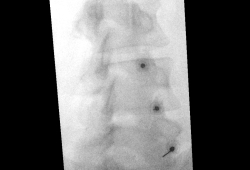

Tijdens de procedure

De behandeling gebeurt onder beeldgeleiding (röntgendoorlichting of echografie). U ligt op de buik, rug of zij, afhankelijk van de plaats van infiltratie. Via het infuus kan je een licht verdovend middel krijgen. De huid wordt ontsmet en lokaal verdoofd, waarna de arts de naald positioneert. Vervolgens wordt het medicijnmengsel ingespoten.